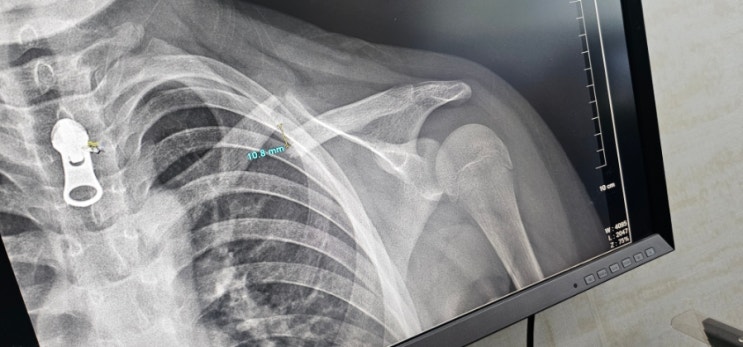

초등학생 쇄골골절 비수술 3달째

누군가에게는 그저그런 심심한 하루가 부모가 되어보니 아이들 아플때가 시간도 더디고 막막한 하루가 될때...

초등학생 쇄골골절 비수술이야기

#어린이 쇄골골절# 쇄골골절#낙상사고#조대병원#기독병원#소아정형외과 #눈물#다치다#11세쇄골골절비수술#...